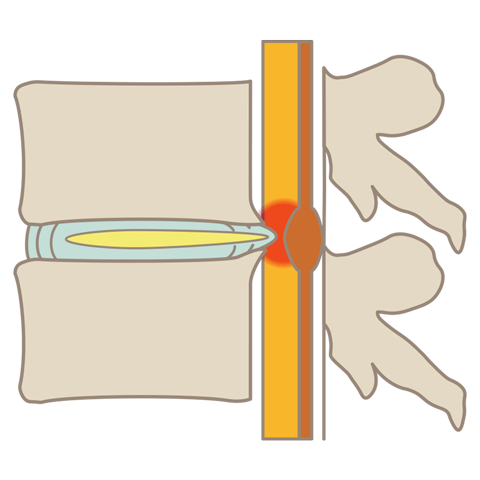

腰部脊柱管狭窄症とは、背骨にある神経の通り道「脊柱管」が狭くなる疾患です。腰痛や足の神経障害、歩行困難などの症状を引き起こします。